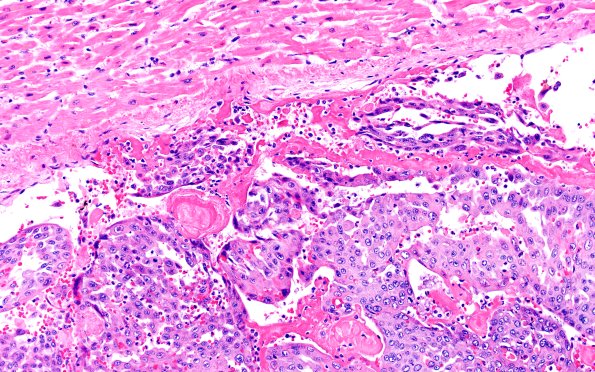

23B2 Heart (Case 23) H&E 1GRV1 20X

The tumor is loosely attached to the ventricular lining. (H&E)